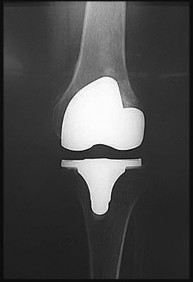

Question 16:

A 65-year-old man presents with anterior knee pain and a feeling of instability during stair climbing 1 year after a primary total knee arthroplasty. Examination reveals a lateral patellar tilt. CT scan is performed to evaluate component rotation. Which of the following errors in component positioning is most likely responsible for his symptoms?

Correct Answer: Internal rotation of the femoral component

Explanation:

Internal rotation of the femoral component or the tibial component increases the Q angle, leading to lateral patellar maltracking, lateral patellar tilt, and anterior knee pain. External rotation of the components generally improves patellar tracking.